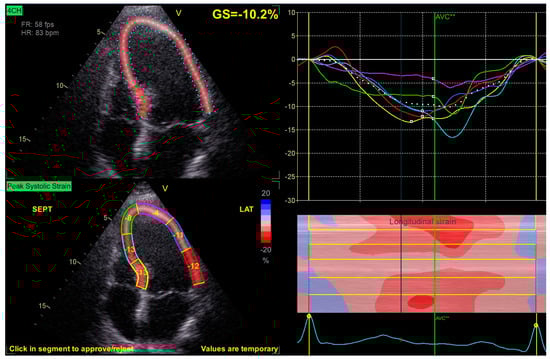

2.2. Speckle Tracking Echocardiography

| RV FWS | −13.3 ± 5.1 | −16 ± 5.0 | −14.2 ± 2.8 | 0.002 |

| RV GLS | −13 ± 5 | −13 ± 5 | −14 ± 3 | 0.639 |

| LV APLAX LS | −10 ± 3 | −10 ± 3 | −9 ± 2 | 0.900 |

| LV 4Ch LS | −10 ± 3 | −10 ± 3 | −10 ± 2 | 0.923 |

| LV 2Ch LS | −9 (−12–−7) | −10 (−14–−8) | −8 (−11–−7) | 0.791 |

| LV GLS | −11 (−12–−8) | −11 (−12–−8) | −10 (−11–−9) | 0.917 |